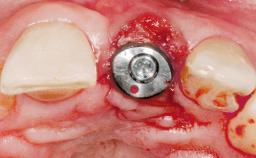

A 36-year-old female patient was referred for the replacement of the upper left central incisor (tooth 21), which had fractured. Although the tooth had been asymptomatic for many years, the crown began to loosen, at which time she presented to her dentist for an assessment. Teeth 21 and 22 had both been endodontically treated many years previously. She was a healthy individual and a non-smoker.

- Surgical SAC classification

- Complex